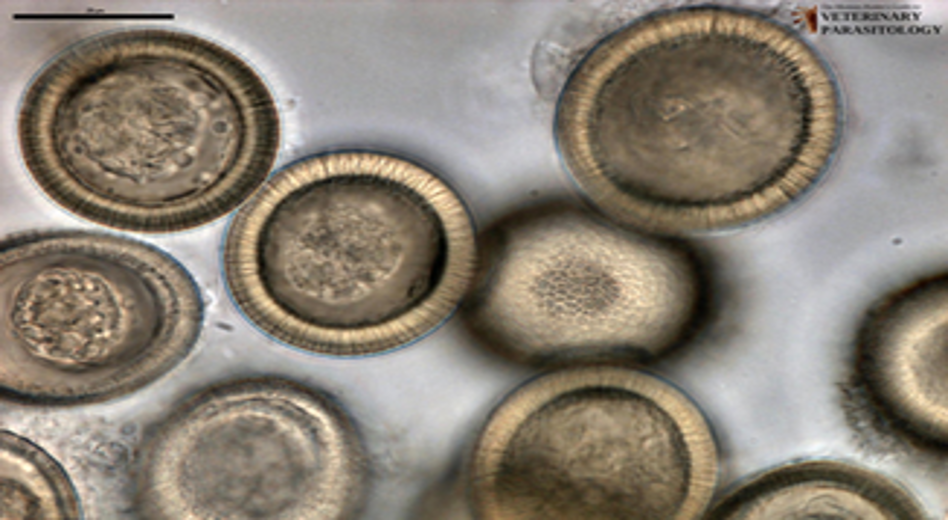

Anoplocephala perfoliata

Host: horses

Intermediate host: grain mites

Location: small intestine, large intestine, and cecum

Transmission: ingestion of infective grain mites

Diagnosis: fecal float

eggs have a 3 layer eggshell

adults can cause granulation tissue at site of attachment

Treatment: Pyrantel paomate and pyrantel tartrate; praziquantel

Zoonotic?: no

Common name: lappeted equine tapeworm